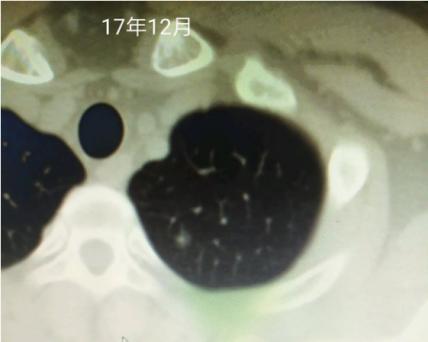

直到根据ct变化明显看到患者结节长大了2-3mm,我判断大概率微浸润了后,才断定可以手术了。手术完后不出所料,微浸润腺癌。

最早只有一个0.6磨玻璃,去年疫情前复查0.8咨询过戴主任您,今年复查变成多发了,麻烦戴主任您帮我看看,这个今年复查的,我们这里还有个女病友去重庆找过您看过,您跟她说的原位,她回来切了果然是原位,佩服得很,托我在这里跟你道个谢,感谢您!

大概率微浸润了。楔形切除小手术还可以根治。

今日大病理出来了,微侵润。走过了5年还是没逃脱挨刀的命,19年肺炎住院查出结节,医生看了发现我17年的体检就有这个结节了,当时恐慌的不行连续好几天没有休息好,出院后到处咨询提心吊胆的,有幸在贴吧碰上戴主任在为病友看片解答,便将自己的片子报告贴在了吧里,没想到主任半夜还给我回复了,因为比较小对比17年的没变化,主任就说先随访,毕竟手术是不可逆的伤害,当时心里一下就踏实就,感觉就是一剂强效安心针,彻底地缓解了自己的焦虑状态。

后面就在吧里看主任的帖子学了很多知识,复查了2年没有变化,本以为会一直这样复查下去没有变化到老去。奈何天不遂意,人生多坎坷,21年底的复查发现由原来的0.6变大成0.8了,还在别的位置多发了结节,当时复查的医生看了对比20年的片子说没有多大变化建议随访。但是我看戴主任说的有变化就要谨慎对待,所以我又将片子报告传到贴吧请求主任再帮我看看,还是一样的,主任大晚上给我回复了,判断我的现在大概率原位小概率微,看到这里我知道我不能等了,因为疫情没办法去找主任亲手解决问题,就在华西挂了号,主刀医生看我的确实有变化也就给我排了手术。手术做的很成功,术中病理报的腺癌,这个有心理准备还好,因为主任给我预估了我的病理,今天去取了大病理微侵润,我以为我的会是原位的,唉。人生不如意之事太多太多了,这里还是要感恩戴主任,让我无比坚决的要去手术,不然又不知道拖到什么时候了,感谢,感谢!这个是大病理,麻烦戴主任再给我看看。